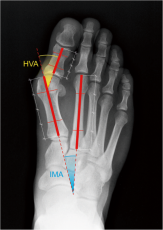

• Χειρουργικής Άκρου ποδός εστιάζοντας σε κοινές παθήσεις και παραμορφώσεις